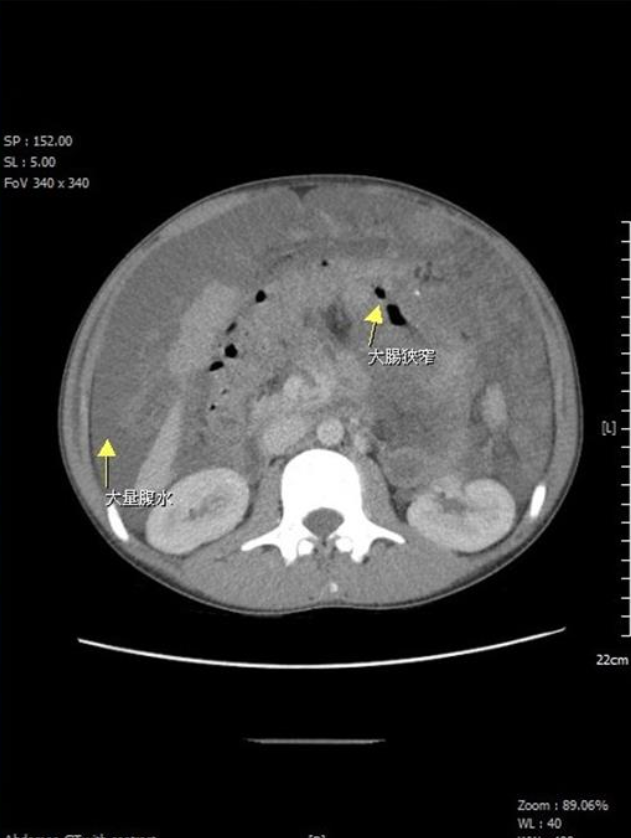

台灣苗栗一名15歲少年,近月持續腹脹不適、身體虛弱、體力下降,日前更因腹脹不適到苗栗縣大千醫院求醫,外科部主任馮啟彥經檢查發現,少年有嚴重貧血和大量腹水,抽血檢驗癌症指數CEA高達16(正常值小於5),進一步安排電腦斷層穿刺和大腸鏡切片後,證實少年罹患末期大腸癌,且癌細胞已在腹腔擴散。